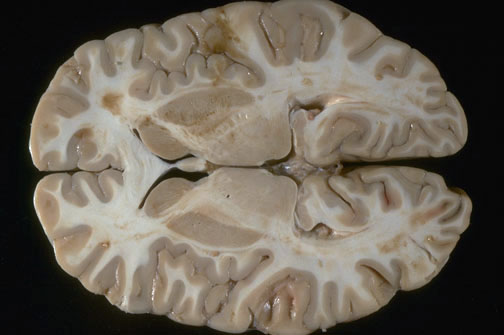

| Identify the following regions of the brain on transverse section by clicking in the image below:

Head of the Caudate Nucleus - Lentiform Nucleus - Hippocampus - Pulvinar of Thalamus - Internal Capsule, anterior crus - Internal Capsule, posterior crus - Fornix - Genu of the Corpus Callosum - Thalamus - Pineal Gland - Optic Radiation |  |